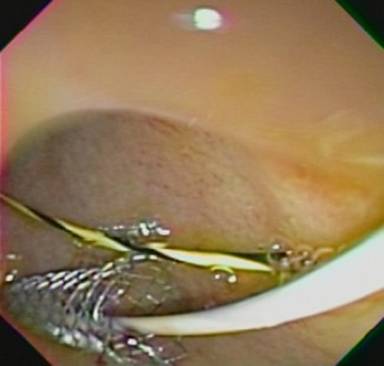

Upper endoscopy had previously shown duodenal stenosis due to circumferential ulcerated and infiltrative lesions in all cases. Facing a high probability of an unsuccessful ERCP, we discussed the possibility of endosonography-guided biliary drainage and duodenal stenting with the surgical and oncological teams. We performed the procedure following the same sequence in all cases. For the whole procedure, the patient was under general anesthesia and fluoroscopic guidance was used. A therapeutic duodenoscope (TJF-160, Olympus, Tokyo, Japan) was introduced and advanced until the duodenal bulb. A 0.035 guidewire (Jagwire®, Boston Scientific, Natick, MA, USA) was advanced through the duodenal stenosis until the proximal jejunum (Figure 1). The stenosis was dilated with a dilation balloon (CRETM Balloon Dilator, Boston Scientific, Natick, MA, USA) until 15 mm. The duodenoscope was advanced but the major ampulla could not be identified. The guidewire was left in place and the duodenoscope was removed. A linear array echoendoscope (GF UCT-140, Olympus, Tokyo, Japan; Alfa 5 processor, Aloka, Tokyo, Japan) was introduced. Endosonography examination was performed to look for the dilated common bile duct, the largest left intrahepatic duct and the presence of collateral veins. In all cases, the largest left intrahepatic ducts were smaller than 6 mm and we did not attempt the antegrade transhepatic access. The common bile duct was punctured with a 19-gauge needle (EUSN-19T, Cook Medical, Bloomington, IN, USA) (Figure 2). Bile was aspirated and contrast was injected to confirm an adequate position of the needle (Figure 3). After confirmation with fluoroscopy, a 0.035 guidewire (Jagwire®, Boston Scientific, Natick, MA, USA) was advanced through the needle into the common bile duct and the needle was retrieved. A 6-Fr cystotome (Endo Flex, Voerde, Germany) was then inserted over the guidewire to create a bilioenteric communication (Figure 4). In four patients, a partially covered biliary self-expandable metallic stent (WallFlex® 60/100 mm, Boston Scientific, Natick, MA, USA) was inserted into the common bile duct and successfully deployed, creating a choledochoduodenal fistula (Figure 5). In one patient (Patient#2), we deployed an uncovered biliary metallic stent (WallFlex® 60/100 mm, Boston Scientific, Natick, MA, USA). The echoendoscope was removed and the duodenoscope was introduced over the duodenal guidewire. A non-covered duodenal self-expandable metallic stent (WallFlex® 120/220 mm, Boston Scientific, Natick, MA, USA) was inserted over the guidewire and deployed in all patients (Figures 6 and 7).

Figure 1. Duodenal stenosis. |

Figure 2. Common bile duct punction. |